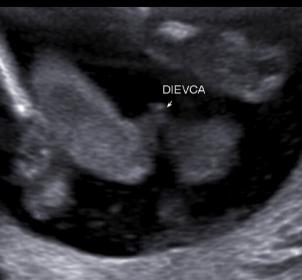

does anyone have similar picture around 20w? Is this 100% girl...okay let`s say 99,9% :) Or anyone experienced similar shot and later turned out boy? Thank you.Attachment 30779